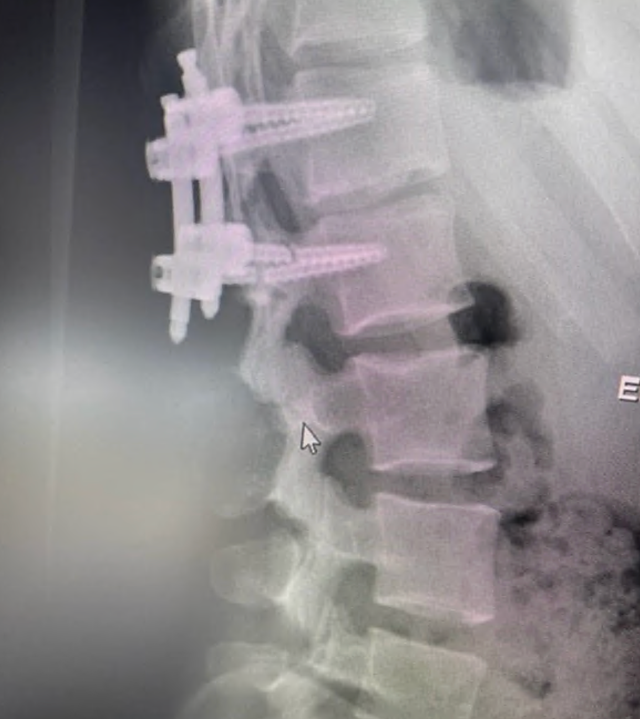

For carefully selected patients with persistent SI joint dysfunction, robotic fusion may provide a definitive stabilization option after conservative and minimally invasive treatments have been exhausted.

A 21-year-old active gymnast with hypermobility, several years of back pain, and severe SIJ tenderness underwent multiple prior treatments before robotic sacroiliac joint fusion led to good pain improvement and return to reasonable normal activity.